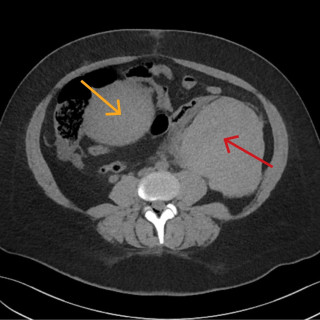

CT-bildene er fra en undersøkelse med opptak uten intravenøs kontrast. Bildet til venstre viser høy attenuasjon i myokard i venstre ventrikkel, og i mindre grad i høyre ventrikkel. Attenuasjonen er tilnærmet lik skjelett i bildet, og tettheten kan passe med forkalkninger. Opptaket er gjort på en spektral-CT, som har økt mulighet for å differensiere mellom ulike vevstyper. Maskinen utnytter de ulike energinivåene i røntgenstrålen, og den kan skille mellom grunnstoffer som jod og kalk utfra absorpsjonsnivået, da begge gir høy attenuasjon. Kalksuppresjon, vist på bildet til høyre (B), bekrefter...